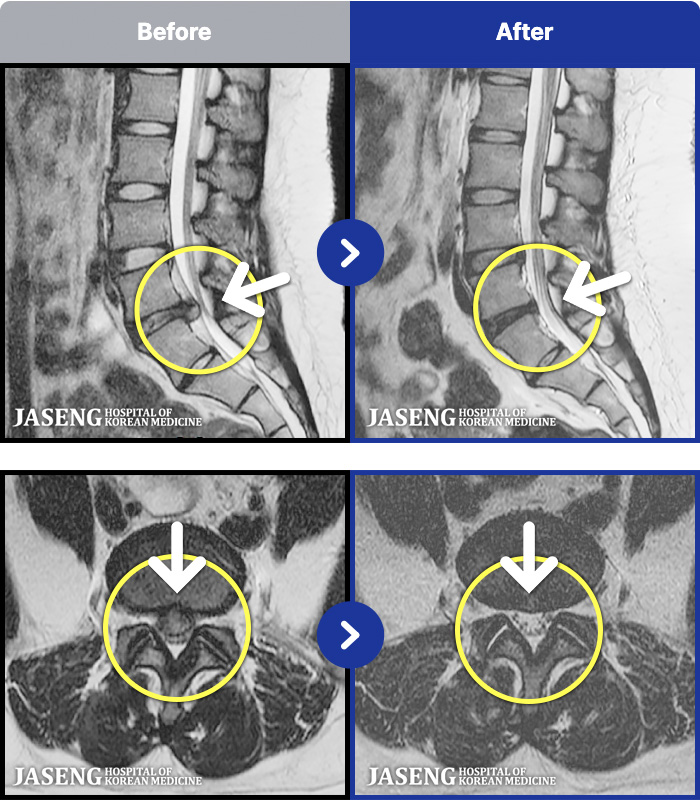

1,293 MRI ũ ʸ Ȯϼ.

Ϻ ߿ Ͽ, ٸ ٱ Ƹ ݵǾϴ. |